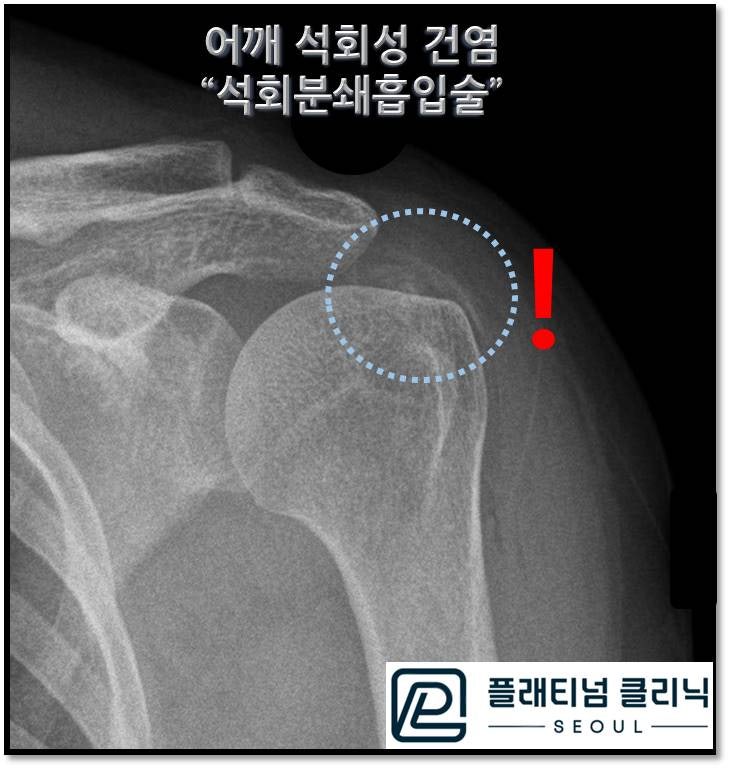

시술 직 후 X-ray 사진을 보면 시술 전 보이던 석회덩어리가 보이지 않고 미미하게 남은 석회만 관찰됩니다.

시술 전 후 X-ray를 같이 비교해 보면 석회가 흡입되어 없어진 것이 확연하게 확인됩니다. 약간 남은 석회의 경우 체외충격파 치료를 통해 충분히 제거하고 흡수시킬 수 있습니다. 석회성 건염의 치료 방법은 아래 링크를 참고해 주세요. https://blog.naver.com/9690067/222801103857